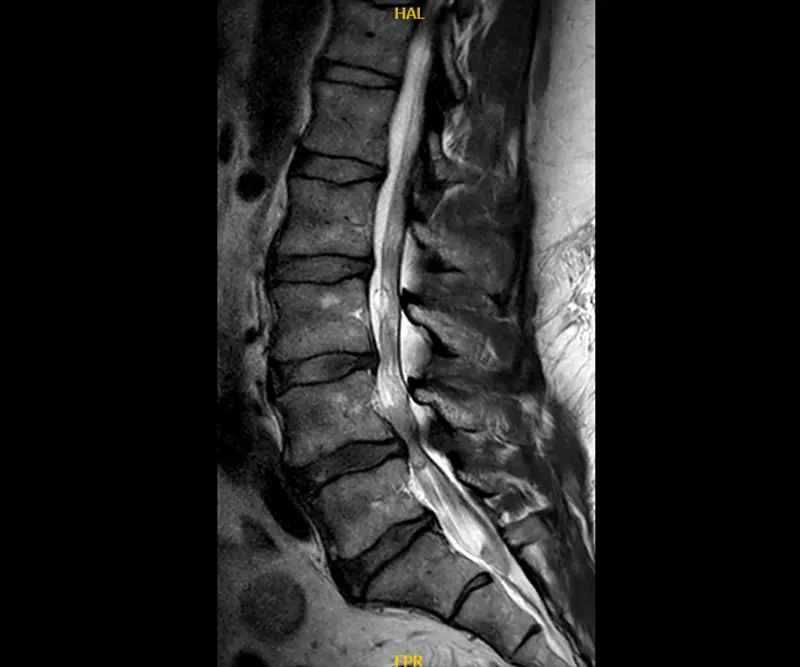

Pre-operative MRI showing the spinal tumor at L5/S1 on the left side.

Bernard actually had two unrelated spine issues happening at the same time. He had a 1.5cm benign schwannoma – a tumor in the lining of the spinal nerve cells – at the L5-S1 level that was compressing a nerve on his left side and causing pain down his left leg.